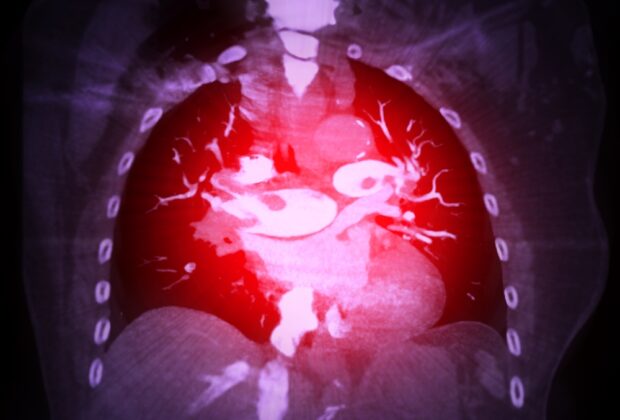

Plaučių embolijos priežastys ir rizikos veiksniai

Plaučių embolija – tai rimta būklė, kai į plaučių arteriją ar jos šakas patenka ir ją užkemša svetimkūnis. Dažniausiai tai ...